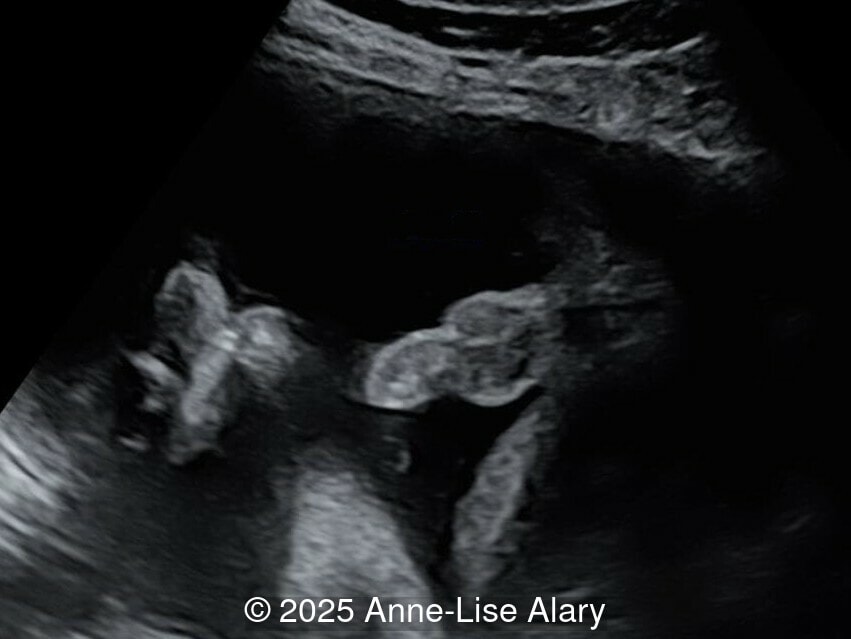

Axial image of the perineum

Image 4 Axial image of the perineum

Our prenatal ultrasound revealed a male fetus with megabladder, dilation of both ureter and kidneys, and thinned kidney parenchyma consistent with Lower Urinary Tract Obstruction (LUTO).  Additional findings suspected on ultrasound and confirmed on computed tomography included:

• Dysostosis: Hemivertebrae L3, fused L4-L5, abnormal left foot with short metatarsals and missing phalanges